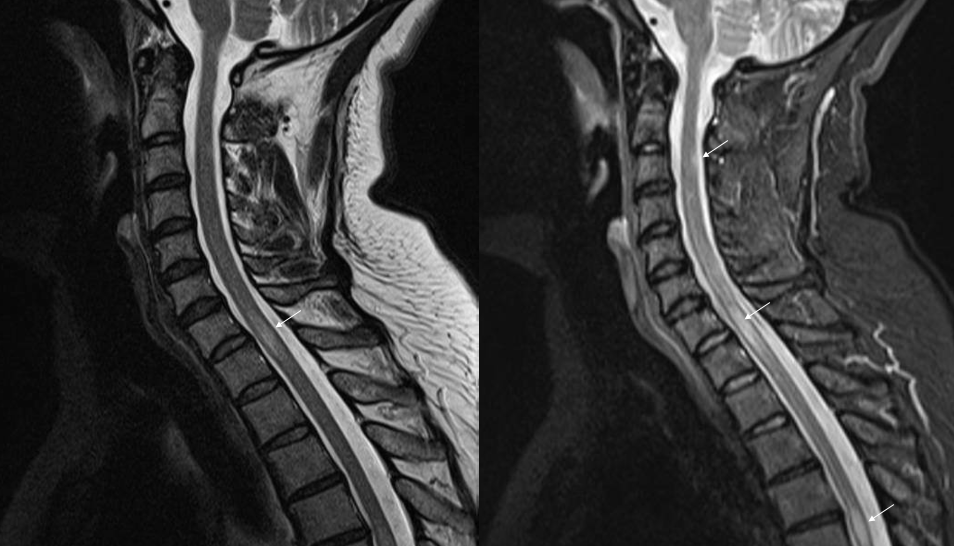

La más conocida es la esclerosis múltiple. Afecta más habitualmente a adultos jóvenes, siendo los síntomas visuales, motores o sensitivos los más frecuentes. Lo primordial es diagnosticarla cuando da los primeros síntomas, para no demorar un tratamiento, habitualmente de administración hospitalaria, que hoy por hoy tiene múltiples posiblidades y alcanza una gran eficacia, evitando así la progresión de la enfermedad y la acumulación de secuelas.

En fases más avanzadas de la enfermedad, que observamos cuando el diagnóstico ha sido tardío o en los cada vez menos frecuentes casos con mala respuesta a las líneas terapéuticas existentes, pueden aparecer otros síntomas como el dolor, la espasticidad o la disfunción esfinteriana, que también tienen tratamientos específicos para mejorar la calidad de vida.